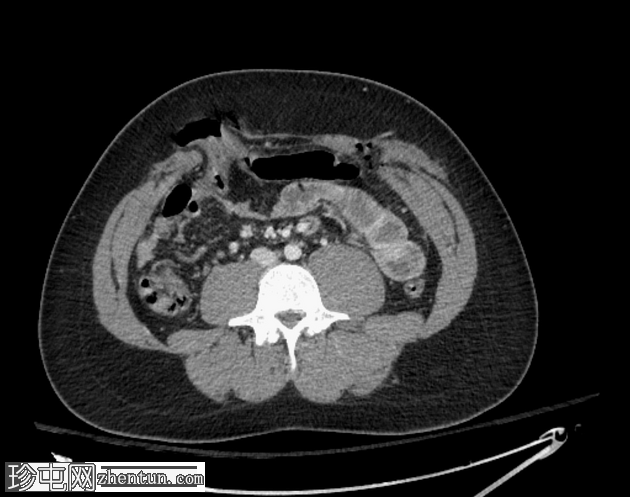

轴位增强扫描(门静脉期)

气腹伴复杂性腹膜积液,提示全层肠损伤。

前腹壁多处刺伤,横结肠和肠系膜经右侧和左侧腹直肌鞘中部疝出。

左侧后方分层血胸。